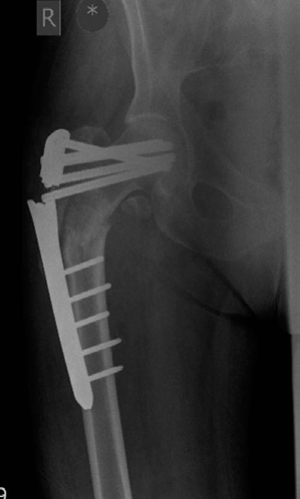

Minute 4 EXAMINER : You fixed it with this recon nail. What do you think about your check X-ray? (Figure 8.12.) CANDIDATE : As I mentioned earlier the literature reports better results with the use of a cephalomedullary nail. I hope that when the recon nailing was performed bone grafting to the fracture site was performed as well so as to address both biomechanics and biology. The cephalomedullary nail is in slight varus and there is some translation at the fracture site. The screws in the proximal fragment are a bit superior to where I would normally like them. The screws are not absolutely parallel and I would study my lateral radiographs carefully to make sure that the screws have not missed the head.

Minute 5 EXAMINER : How will you follow-up this patient? CANDIDATE : I would follow-up this patient with clinical reviews and serial radiographs until the fracture heals. I would start her weightbearing as able, stop NSAIDs, counsel against smoking

if she does, keep an eye on her inflammatory markers and do serial radiographs 6 weeks apart. If there is no callus formation at 3–4 months, I would consider revising the intramedullary nail with autologous bone grafting.